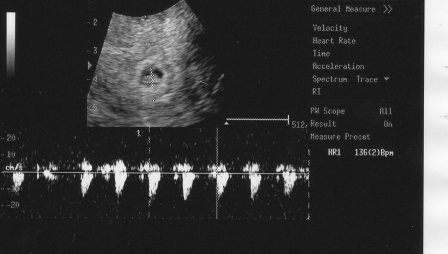

megultrahangozott és elkzdtem mondani az elözményekt( egy szülés, 3 vetélés, gyógyszerek…) nagyon figyelmes volt aztán néztük a monitort. hát sajnos az elötte napi ultrahanghoz képest a petezsák sajnos kezd belapulni, a felsö részénél kicsit beesett viszont volt benne szikhólyag- ami elözö nap nem volt- szépen látható volt. keringés még nem volt, megnézte olyan piros-kék módszerrel is amit az ultrahangon betud kapcsolni. mondta hogy az sajnos nem jelent jót ha belapul a petezsák, de még akármi lehet. azt is mondta hogy ennyi vérzés is belefér még lehet a beágyazódástól (?). hétfön a petezsák 13 mm volt most meg mivel ovális lett 12×18mm. nem kell feküdnöm, azt mondta ebben az esetben ez ugysem segit. azért dolgozni ne menjek.azt is megbeszéltük, hogy ha nem fejlödik és újra kell probálkoznunk akkor milyen elözetes kivizsgálások vannak amit az elözö doki nem csinált meg

de elötte még csütörtökön este 8ra menjek. megnézzük milyen irányban fejlödik. vettek este vért hogy a péntekihez képest hogy változik a hcg-m mert az is mutatja az irányt. bizom benne, hogy minden rendben lesz, mert születtek már egészséges babák ovális petezsákból is. a gyógyszerekröl is beszéltünk azt mondta ugyanolyan jó a duphaston mint az utrogestán. viszont ilyenkor azért nem lehet közben hormont nézni, mert állitólag a szervezet semmi sárgatestet nem termel csak a gyógyszer. azért nem szabad abbahagyni!!!!!